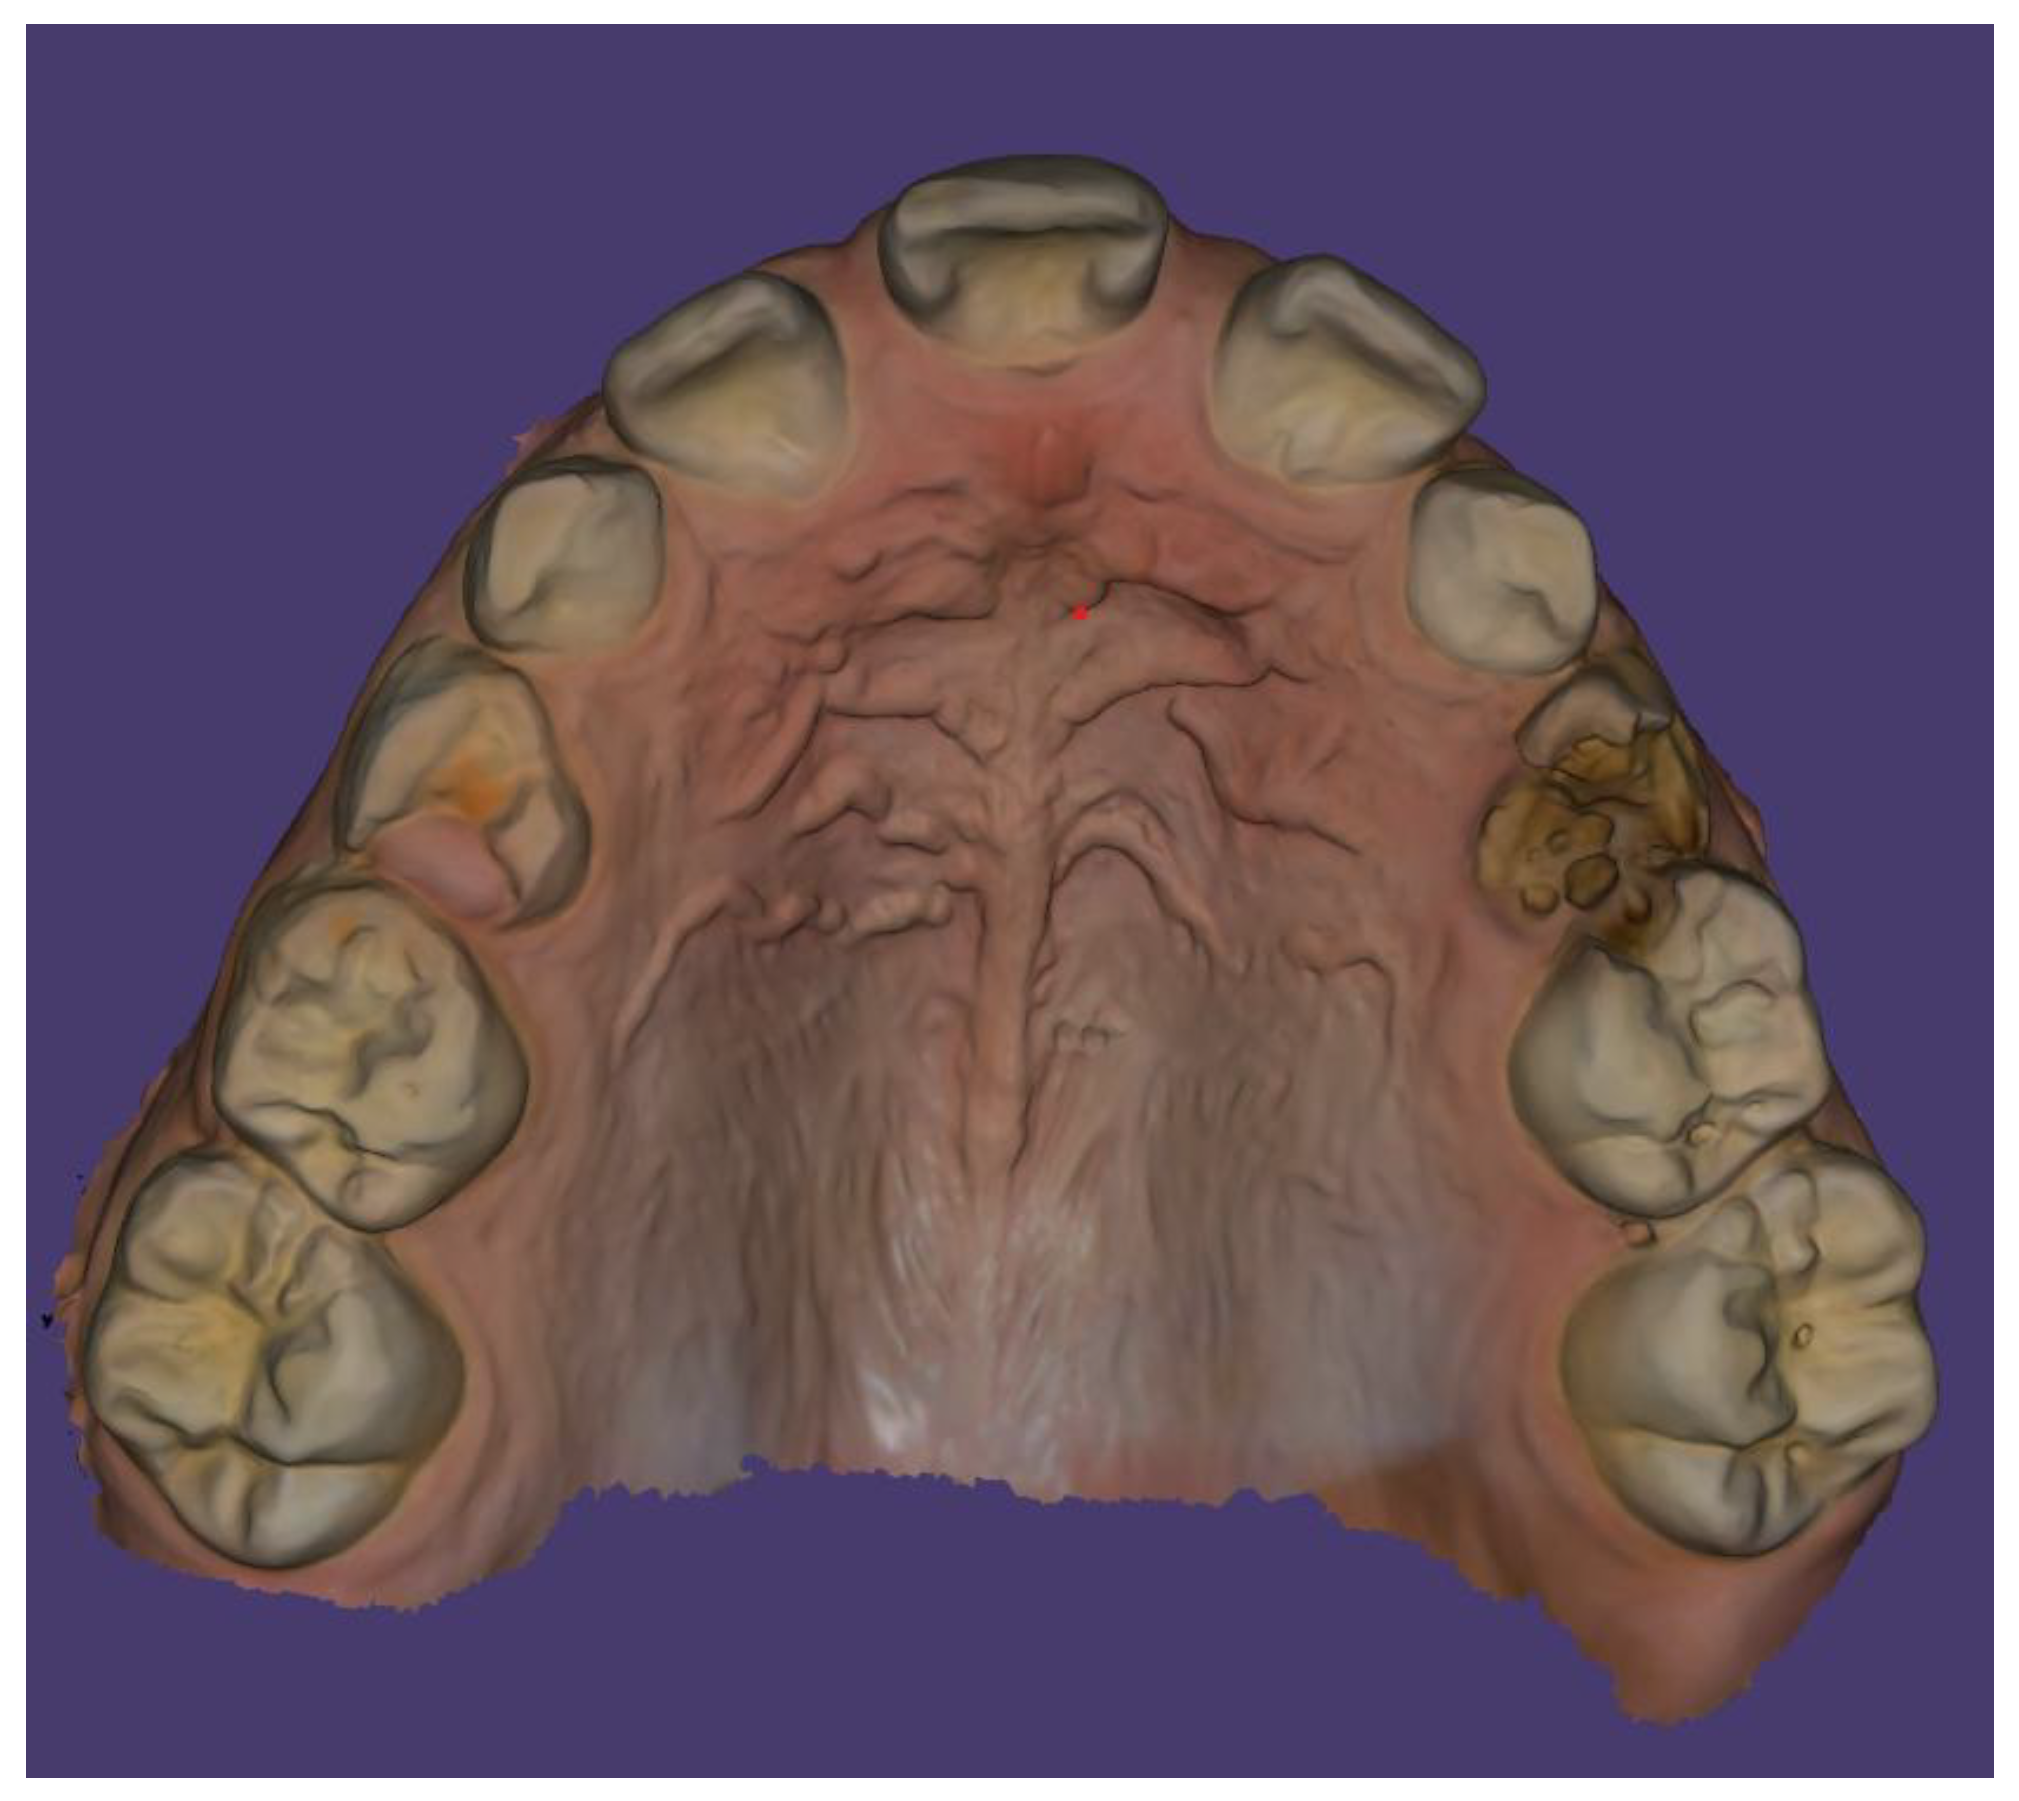

Case Description